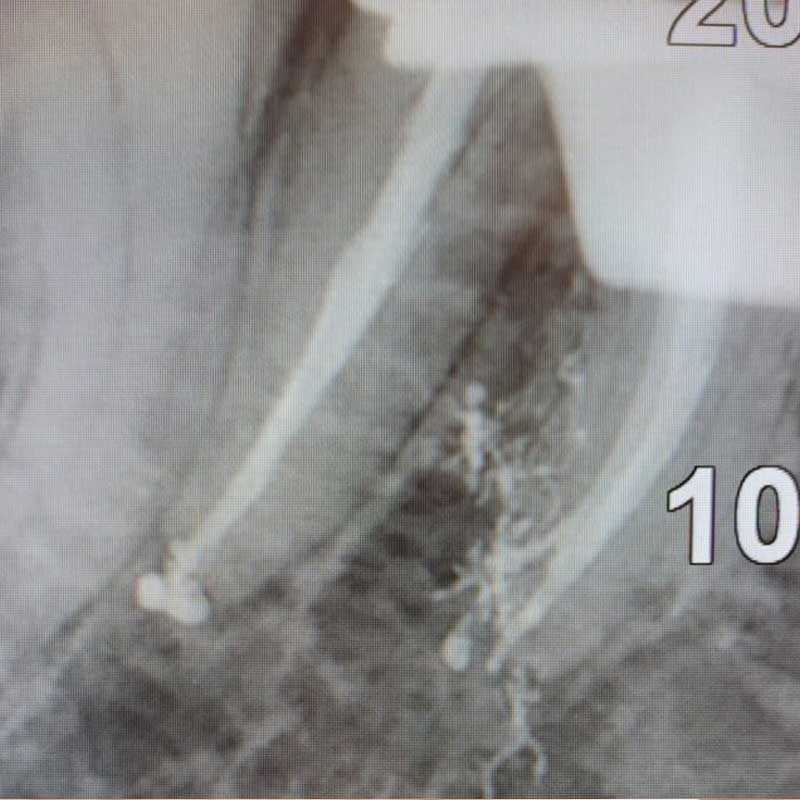

L’ENDODONZIA

L’endodonzia si occupa dei tessuti interni del dente, in particolare della polpa dentale contenente nervi e vasi sanguigni. Quando la polpa è infetta o danneggiata, si interviene con una terapia canalare (devitalizzazione): diagnosi, anestesia, asportazione del tessuto, pulizia, disinfezione e sigillatura dei canali radicolari per salvare il dente.